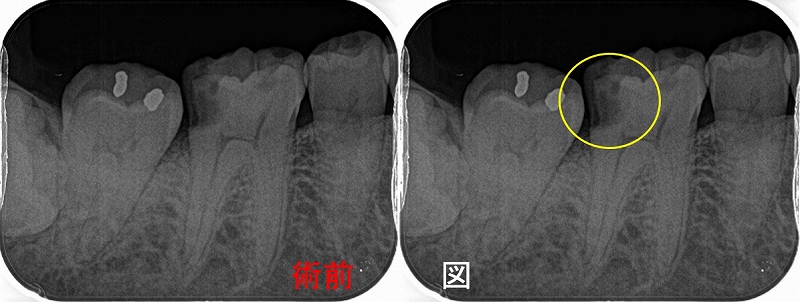

レントゲン

2026 EEdental NAY (1).jpg

第1大臼歯の黄色丸:C2~C3に及ぶ虫歯

第2大臼歯の赤丸:C4に近い虫歯

前に患者さんにも言いましたが、成功率を高くする為には

基本1つ次のステップの治療を行う事

つまり第1大臼歯は神経を取ってクラウン

第2大臼歯は抜歯

こうすることで将来トラブルの出る確率は多少減らせますが、

歯の寿命は確実に短くなりますし、咬みずらくなります。

ここが残りの人生を考えた際の選択になります。

短期予後を取るか!?それとも長い人生・将来的な事を考えた選択をするか!?

前者の難しい歯の保存を説明なしに行うと、上手く行かなかった場合藪医者扱いを受けるので

最初に患者さんにある程度説明を行い理解をしてもらいます。

まず第一大臼歯はいつも通り

とりあえず神経を残す治療を行い、痛みが後で出てしまったら後で神経を取ると説明

2026 EEdental NAY (2).jpg

さて、この第2大臼歯・・・

縁下に大きく虫歯が広がっており、歯に穴を開けずに虫歯をきちんと取るのが超難度

保存をしても歯根破折、咬合から来る虫歯などが怖いのはあり、

将来起こるであろうこのリスクを下げるには抜歯も1つ

患者さんと話し合い、残す方向で治療を行いました。

2026 EEdental NAY (3).jpg

パフォレーションを起こさせないように虫歯を削るのに50分近くかかりましたが、

一応保存治療が行えました。

この先、数カ月様子を見て問題無ければ本歯を作らせてもらいます。

基本中の基本でもある虫歯を削るって、ホント難しいと感じます(・ω・;)